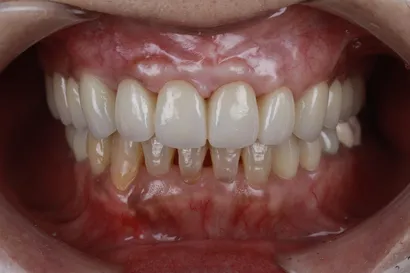

重度虫歯からの全顎インプラント治療

70代 男性

執刀医 Dr.大杉 治療内容 虫歯・歯周病が原因で噛み合わせが崩壊していたので、全顎的なインプラント治療を行い、口腔機能の回復を行いました。

上顎:ピンクポーセレンを用いたフルジルコニアインプラントブリッジ

下顎:奥歯=ジルコニアインプラントブリッジ、前歯=ジルコニアクラウン治療期間 1年6ヶ月 費用 上顎:420万 税抜

下顎:330万 税抜リスク セラミックのすり減りを防ぐために、ナイトガードを作成しています。毎晩使用することで、セラミックを長持ちさせることができます。 -